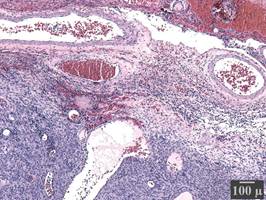

Initial assessment of hematoxylin and eosin (HE) - stained sections showed mild reactive glial proliferation, and the presence of a uniform dense population of spindle to slightly epithelioid cells with ovoid nuclei, small nucleoli and sparse cytoplasm infiltrating the dura (Figure 3). Three mitotic figures in 10 high power fields were identified whereas none was atypical. Architecturally the tumor had a fascicular growth pattern with occasional eosinophilic protein drops. No significant cytologic atypia or infiltration of the brain parenchyma was registered, however small foci of necrosis were noted. Lymphocytic infiltration and foam macrophage cells were evident.

Figure 3 Histopathological investigation: Hematoxylin and eosin stain (x40) of sections acquired from the peripheral part of the neoplasm. Tumor cell infiltration of the dura matter (an endosteal layer of dense fibrous connective tissue, containing a significant number of blood vessels).